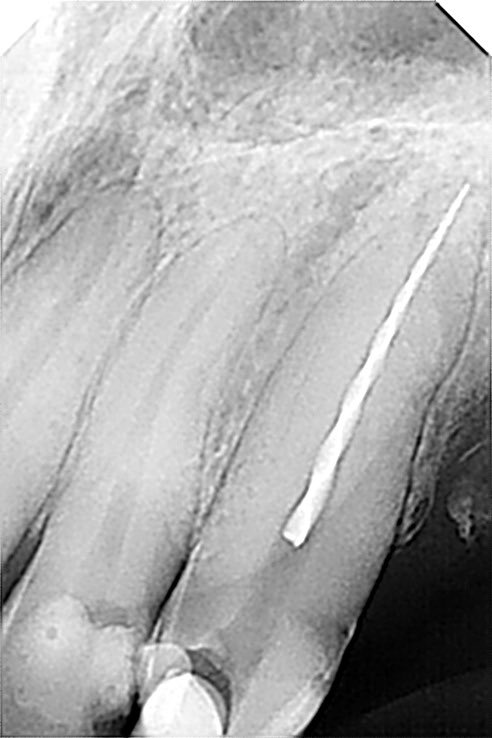

طبيب مقيم في علاج الجذور و عصب الأسنان 🦷 🦷 Endodontic resident at @ksmcmedia 📍Riyadh